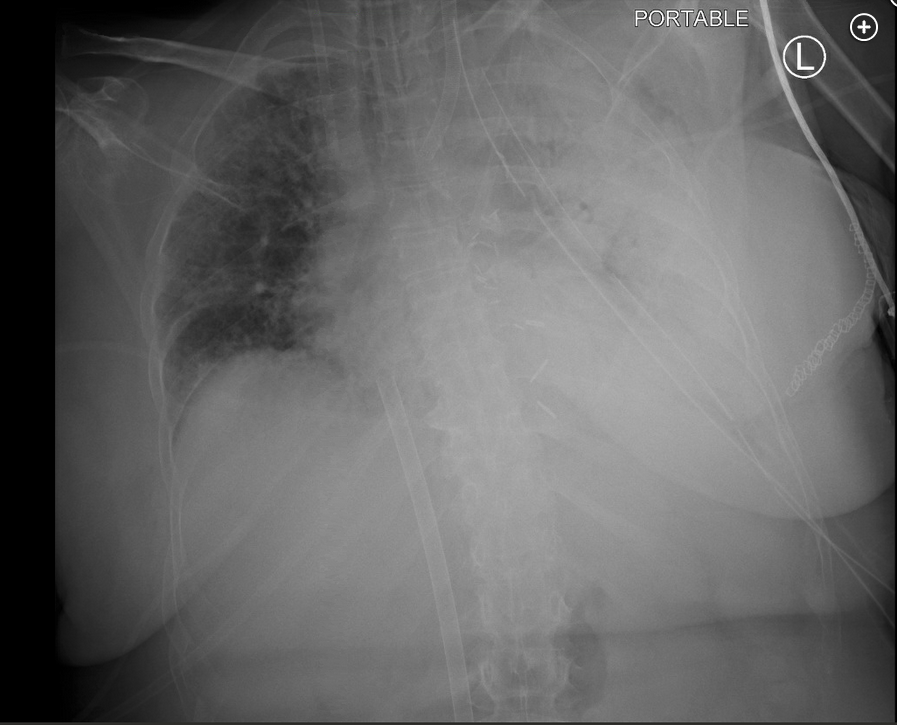

A 50-year-old woman was admitted for left single lung transplant for interstitial lung disease. Her intraoperative course was uncomplicated, with immediate postoperative PaO2 of 306 mm Hg. Upon arrival to the cardiothoracic ICU, she developed acute hypoxemic respiratory failure requiring FiO2 of 1.0, which was associated with new infiltrates in her graft and a PaO2:FiO2 ratio of 89 mm Hg. She was maintained on lung-protective ventilation and placed on venovenous extracorporeal membrane oxygenation (VV-ECMO). No donor-specific antibodies were present. Her oxygenation improved being supported by VV-ECMO, allowing FiO2 to be weaned to 0.40 on the ventilator, but her infiltrates progressed with near-complete opacification of the graft (Figure 1). On postoperative day 1, it was noted that she was no longer spontaneously moving her right upper extremity (RUE) and right lower extremity (RLE). On physical exam, her RUE and RLE did not withdraw from painful stimuli. She underwent emergent head CT scanning. Representative head CT images are shown (Figure 2 and Figure 3).